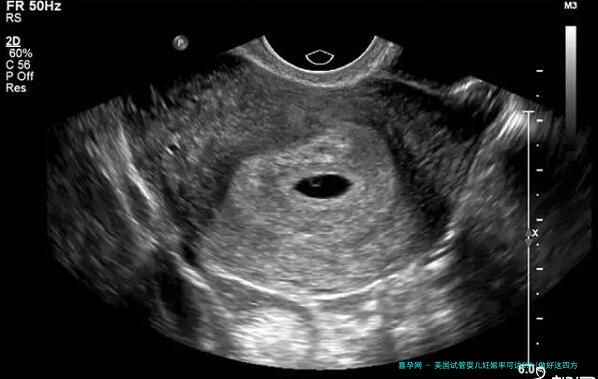

美国试管婴儿技术的成熟和发展让许多渴望享有孩子的家庭看到了期望。与传统的生育方式对比,试管婴儿技术能够有效解决女性输卵管堵塞、精子活力低低级问题,实现生育愿望。近几载来,美国的试管婴儿成功率陆续提升,一些领跑的医疗组织甚至已经达到 60% 以上,为想要通过试管婴儿怀上宝宝的家庭提供了更大的决心信念。

然而,美国试管婴儿的成功率并不是变化多端,它受到许多种因素的影响,例如女性岁数、身体状况、精子品质等。想要提高试管婴儿的成功率,需要做好充沛准备和后期护理。